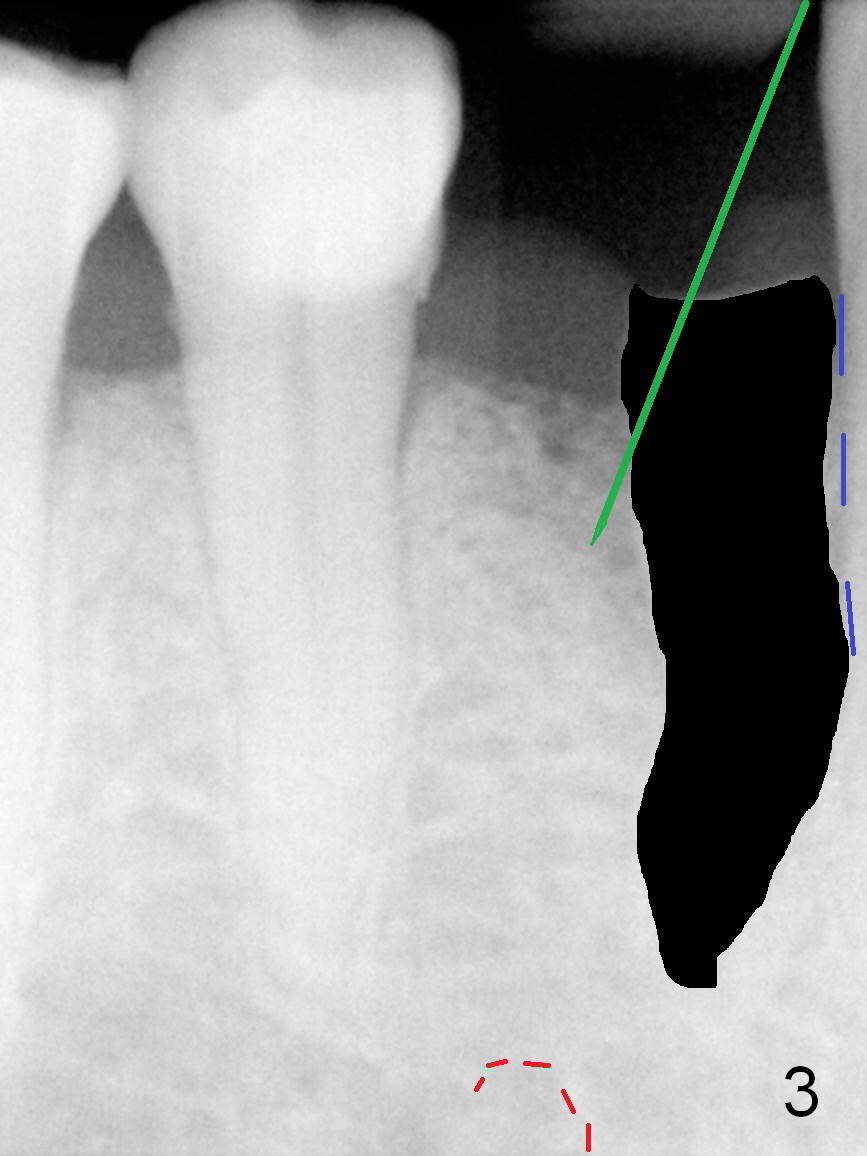

A 73-year-old man requests extraction of the lower right 1st premolar and implant restoration (Fig.1: #28). The root of the affected tooth (Fig.2 black area) is not only curved, but also deviated mesially (close to the root of the canine (blue dashed line). Osteotomy should be established with a sharp 1.5 mm pilot drill obliquely in the distolingual slope of the socket (treated with Metronidazole, Fig.3 (green line)). Once bony penetration is obtained, the drill straightens up in the middle of the socket and along the ideal long axis (Fig.4). Remove the bone in between (Fig.4 pink dashed line) if there is resistance to change in the trajectory. A PA is taken to confirm the position and trajectory. Then extend the osteotomy (Fig.5 green line) , but not beyond the apices of the neighboring tooth and the original socket (brown line), since the Mental Loop is nearby (Fig.2-5 red dashed line).